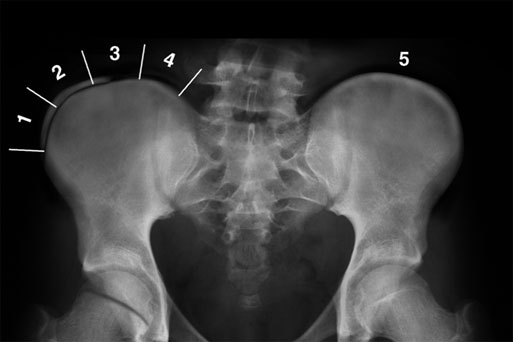

방사선에서도 쉽게 관측할 수 있는 것이 바로 장골골단 입니다.

장골 골단의 골화는 Anterior Superior Iliac Spine 에서 시작하여 Posterior Superior Iliac Spine 까지 진행하게 됩니다. 골골화가 4단계 까지 진행된 후에 완전히 골화가 진행되어 5단계가 되게 됩니다.

각 단계마다 확인해보면 1단계는 25% 이하, 2단계는 25~50%, 3단계는 50~75%, 4단계는 75~100% 골화가 진행되는 것으로 분류하고, 5단계는 장골에 유합되는 것입니다.

아래의 그림은 그렇다면 Risser 3 겠지요? 대퇴골두에도 아직 성장판이 남아 있는 것을 알 수 있습니다.

아래는 Risser 4 사진임을 유추해 볼 수 있습니다. 척추의 성장이 거의 끝난 상태인 것이지요.